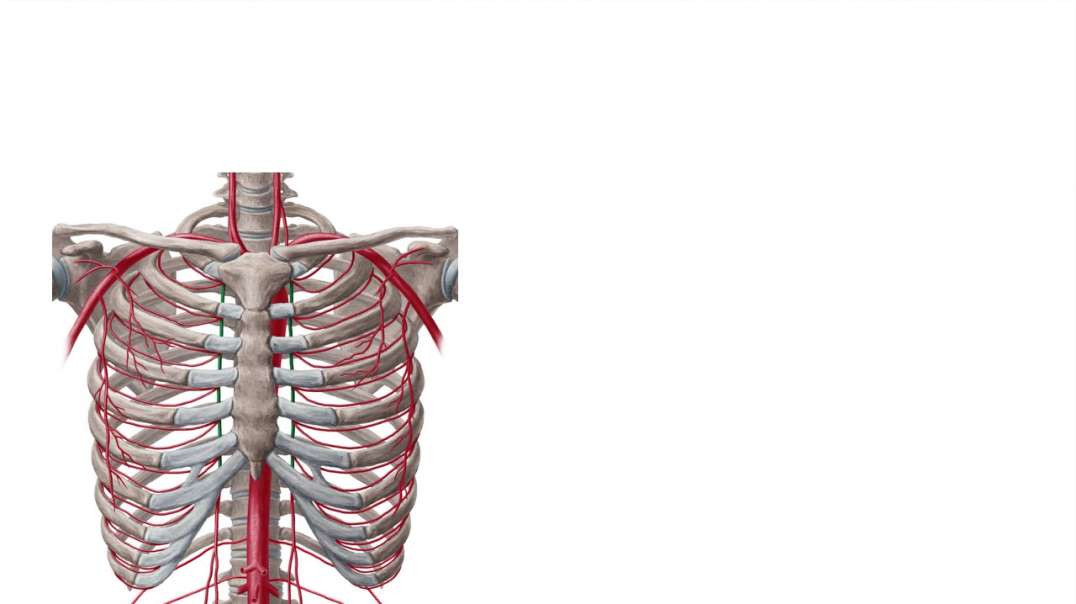

Joints and blood supply of talus

Joints and blood supply of talus kenhub